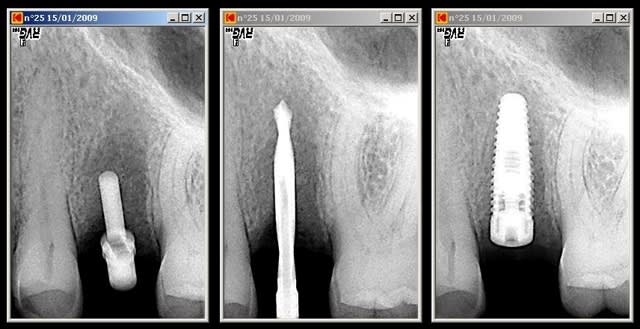

Tiens là aussi contact avec la racine de 26.

Rattrapage aprés retrait et réinsertion de l'implant.

Personnellement, je fais systématiquement une radio avec 1 indicateur de direction en place après avoir passé le foret pilote jusqu'aux 2/3 de la longueur. C'est le meilleur moyen de contrôler l'axe et de le corriger en cas de besoin.

Pour ma part, dans les cas limites, je prends une radiographie systématiquement avec l'indicateur de position (cela permet toujours de rectifier l'axe) et une fois le forêt pilote passé à longueur de forage (rectification très difficile mais au moins cela évite de poser l'implant si on sait que l'on va toucher une racine).